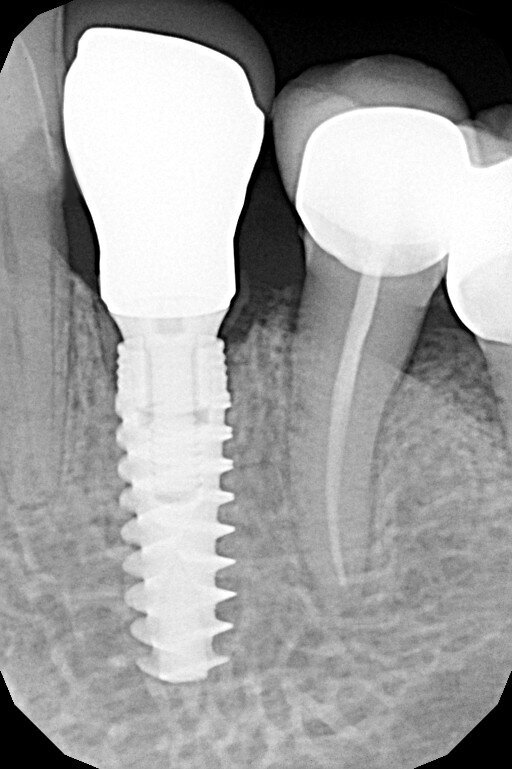

L’esame di primo livello (radiografia endorale) mostra la presenza di un minus dei tessuti calcificati a carico della radice. Si impone per ovvie ragioni un approfondimento volumetrico 3D: soltanto una CBCT ci consentirà di localizzare correttamente la lesione e valutarne la posizione, l’estensione e l’eventuale recuperabilità dell’elemento dentario. Il taglio trasversale della radiografia 3D mostra un riassorbimento radicolare esterno che riguarda la porzione linguale dell’elemento dentario (Figg. 1-4). Il riassorbimento presenta una posizione particolarmente sfavorevole, in quanto si estende già al di sotto del margine osseo crestale su un elemento dentario peraltro già trattato da un punto di vista protesico (Figg. 2, 3). Le opzioni terapeutiche proposte alla paziente sono sostanzialmente due: trattamento endodontico e rifacimento del restauro protesico, previo accesso chirurgico sul lato linguale con allungamento di corona clinica, oppure impianto post-estrattivo con tecnica Socket-Shield. La paziente sceglie questa seconda opzione e firma regolare consenso informato.

Fig. 4_Rx 2d e 3D, con evidenziazione del riassorbimento radicolare, che riguarda l’aspetto linguale e si approfondisce al di sotto del margine della corticale ossea; pianificazione implantare su apposito software di progettazione.

Fig. 13_Rx di fine intervento.

Fig. 20_Rx finale alla consegna della corona definitiva.